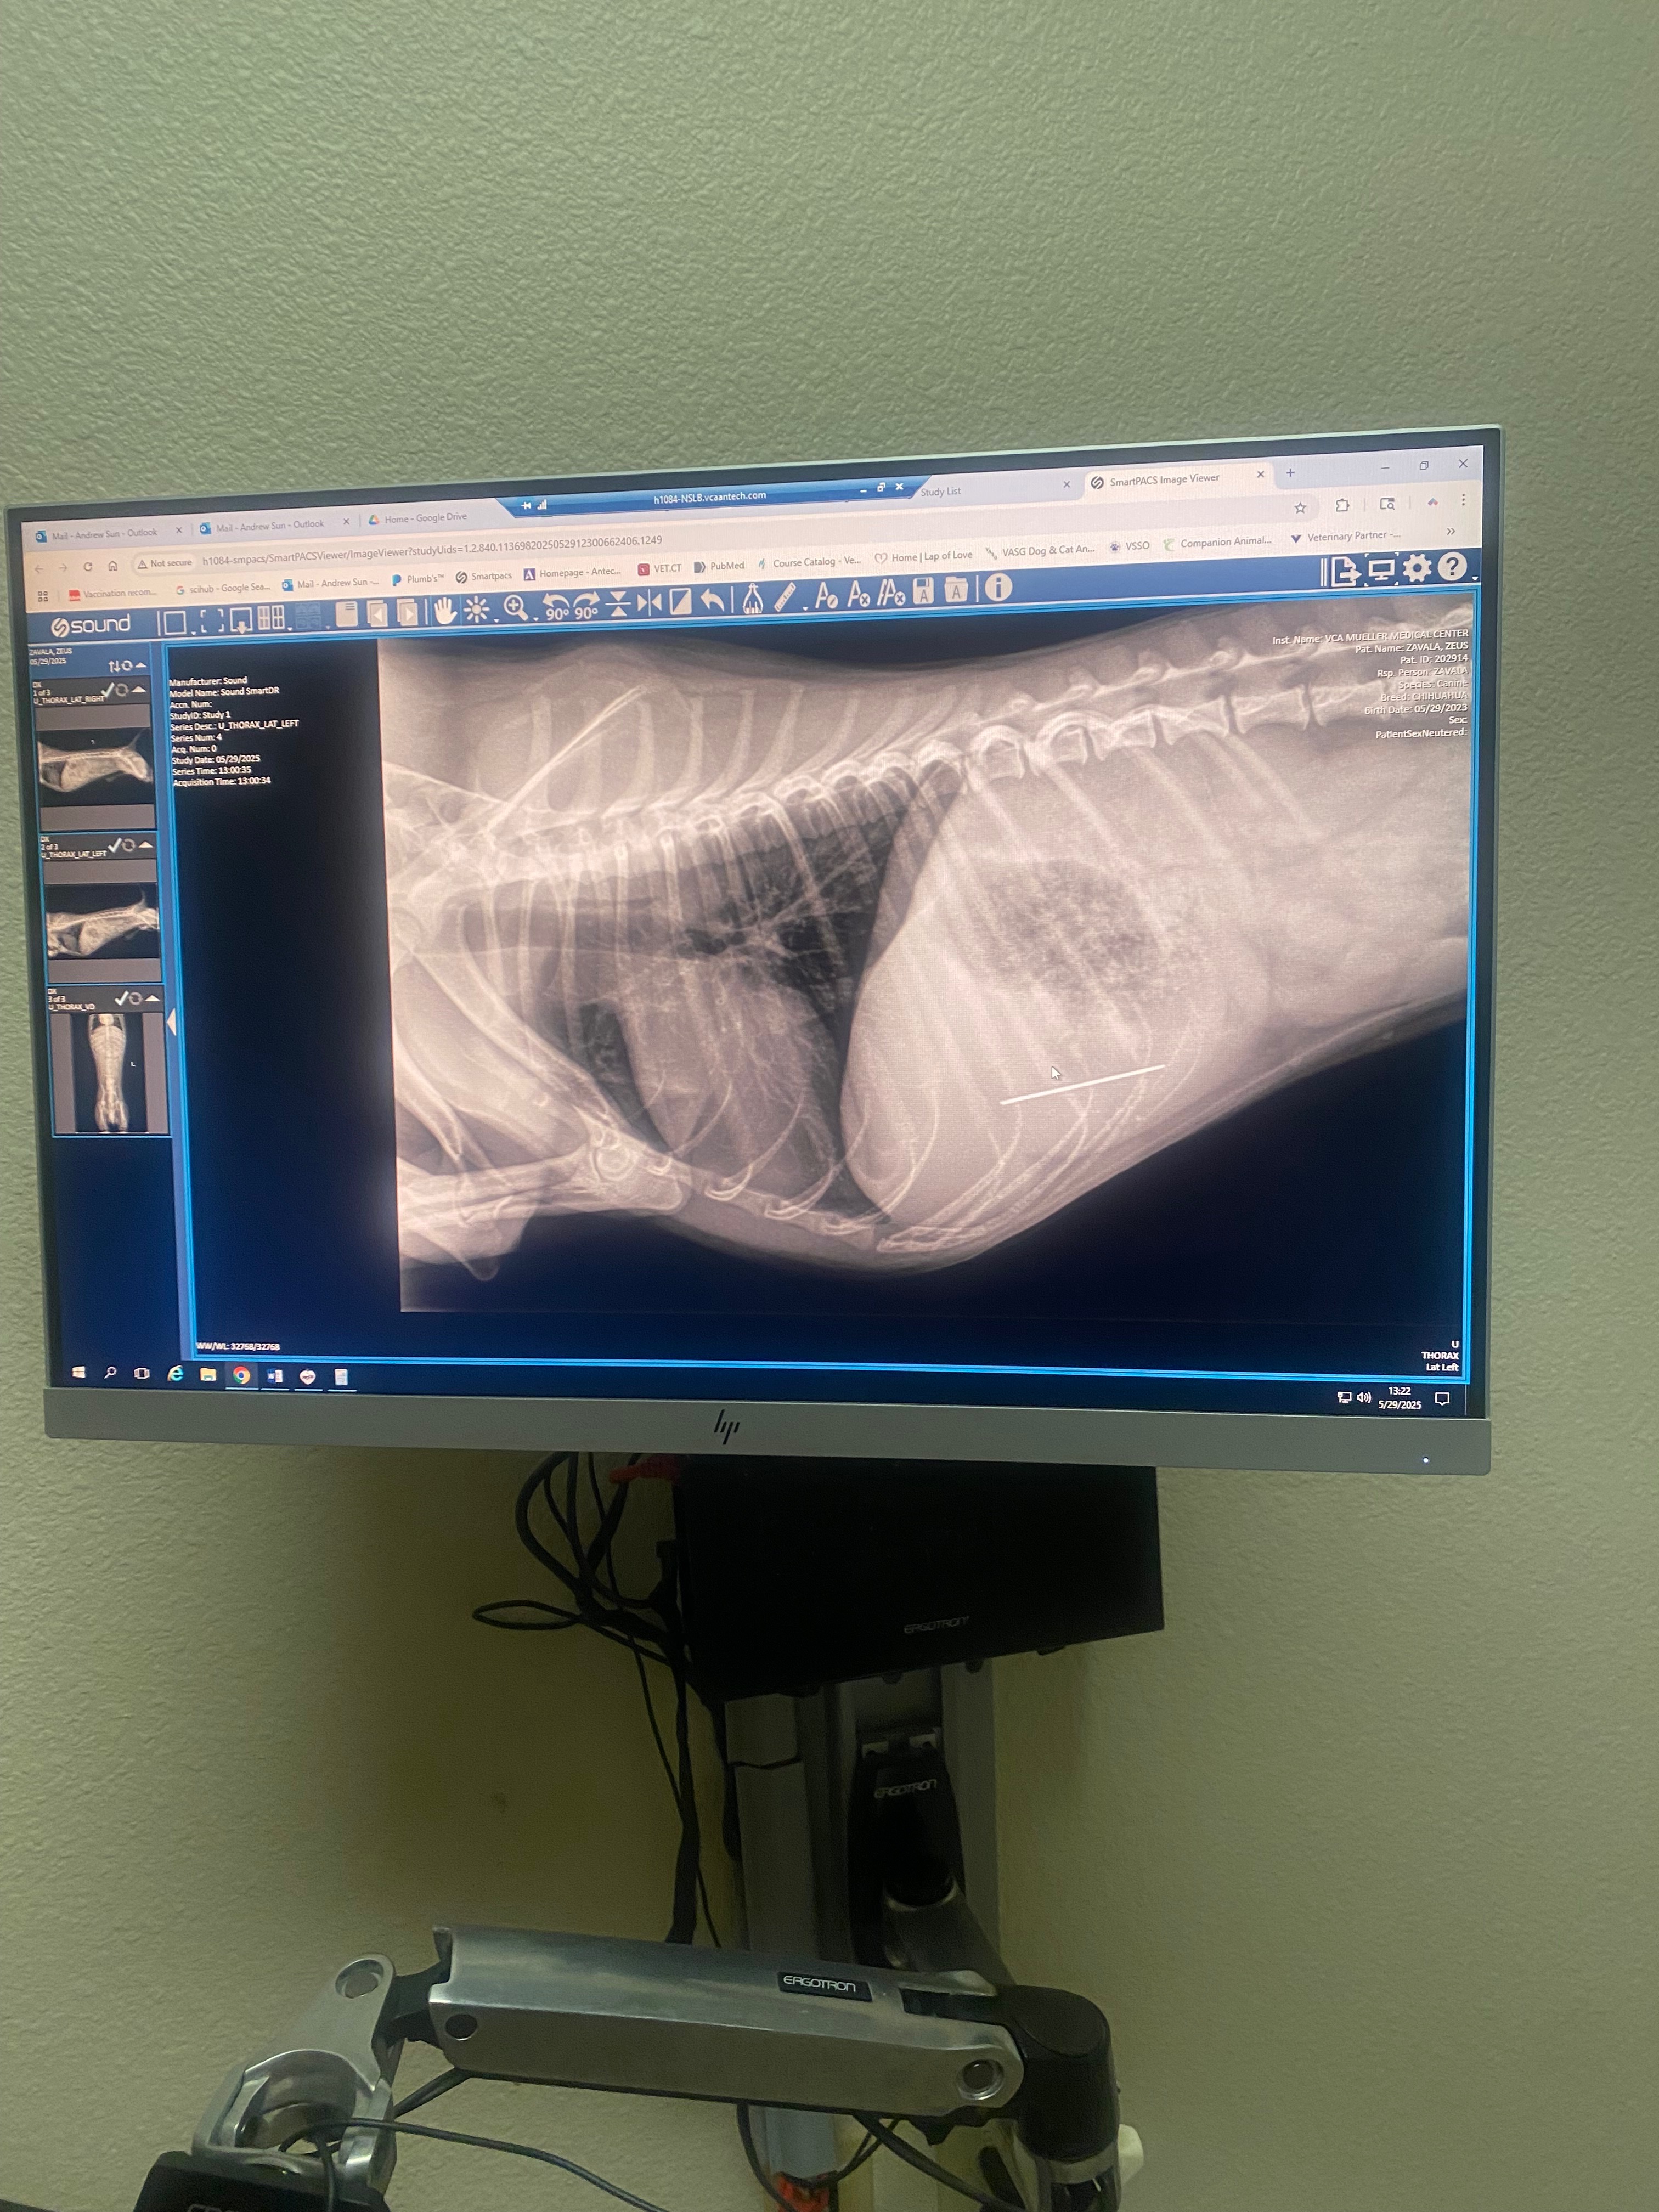

We rushed him to VCA Mueller Pet Medical Center in Sacramento, where they confirmed through X-rays that the needle is inside his body and surgery is the only way to prevent serious internal damage or worse. The estimate for his care and surgery ranges between $5,774.77 and $7,507.20 . As much as I wish I could cover this on my own, the cost is far beyond what I can afford right now.